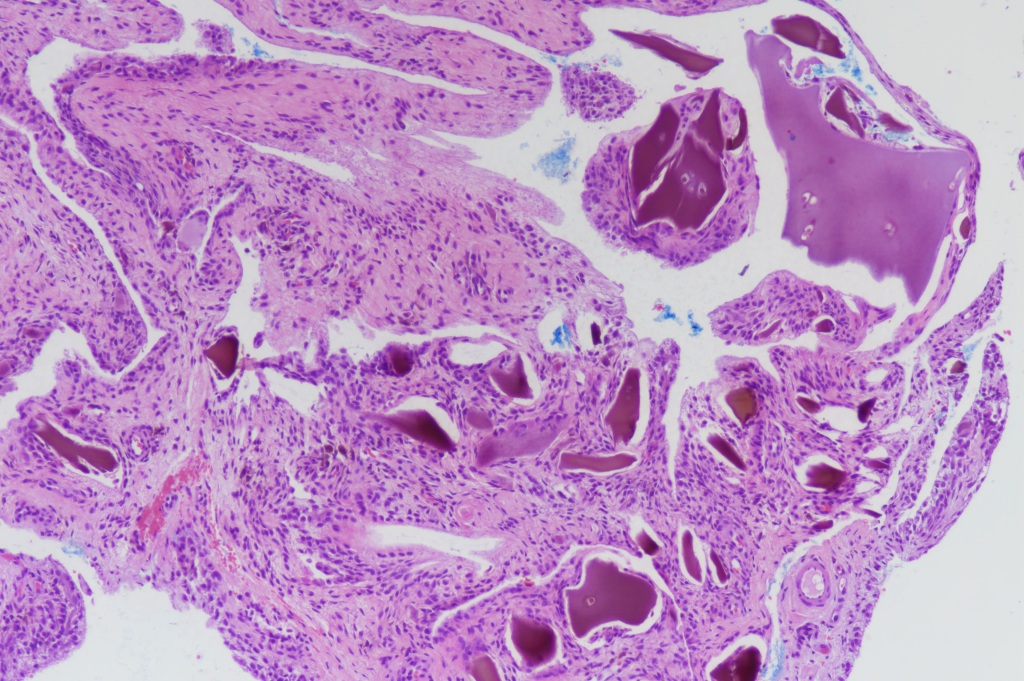

Ochronosis pathology